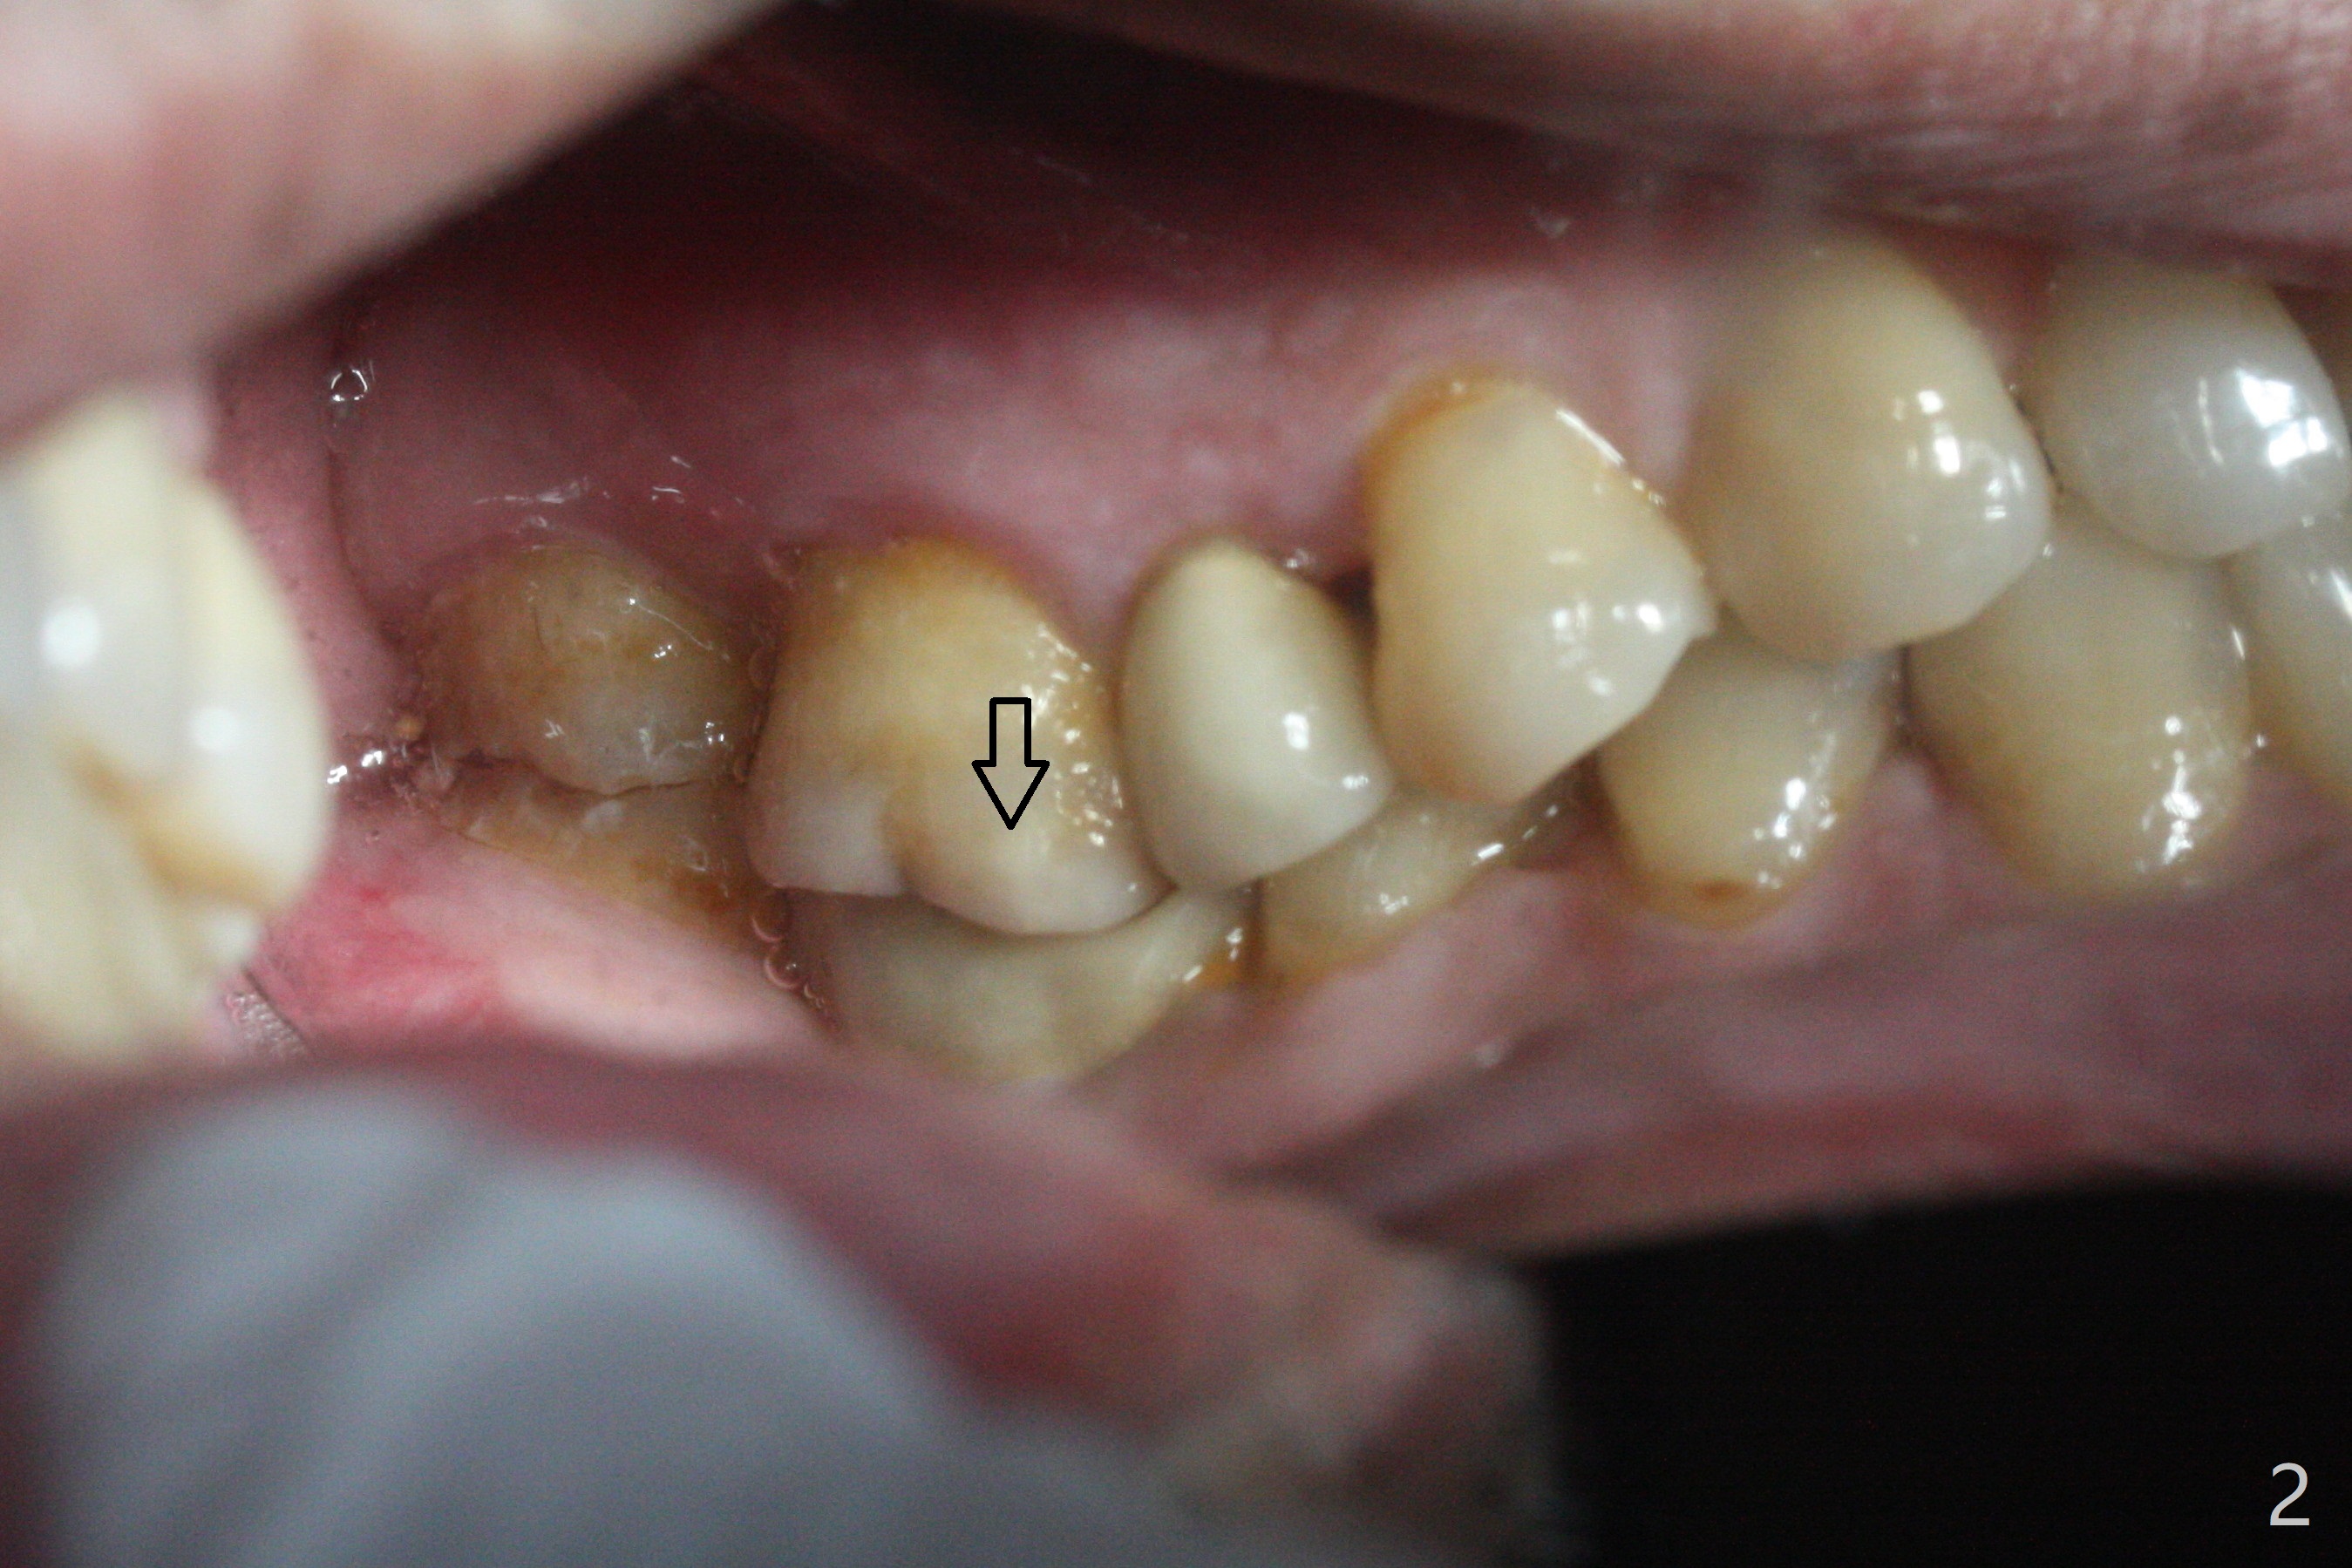

A 62-year-old man complains of food impaction around #19 implant crown one year 4 months post cementation (Fig.1-3). Before redo of the crown with poor mesial emergency profile (Fig.3 *), it appears necessary to correct the supraerupted opposing molar (Fig.1-3 downward arrow) and mesially tilted 2nd molar (Fig.3 horizontal arrow). The tooth #19 had been missing 20 years before implantation, associated with occlusal wear at #18 (Fig.4). For intrusion, composite is placed in the occlusal surface of #19 crown after roughening (Fig.5,6) with occlusal separation of the remaining dentition (Fig.6). The patient is instructed to bite on the left side as much and long as possible (even when he does not eat). Will the tooth #14 be intruded? Is the treatment sufficient?

In fact the tooth #14 appears to have been intruded 2 months post-treatment. The composite dislodges 3 months later. A new crown with screw retained is fabricated, but the patient cannot masticate well on the left. DO caries of the tooth #20 is found (Fig.7) and restored (Fig.8). As a matter of the fact, the food impaction is reported between #18 and 19! What can we do now?